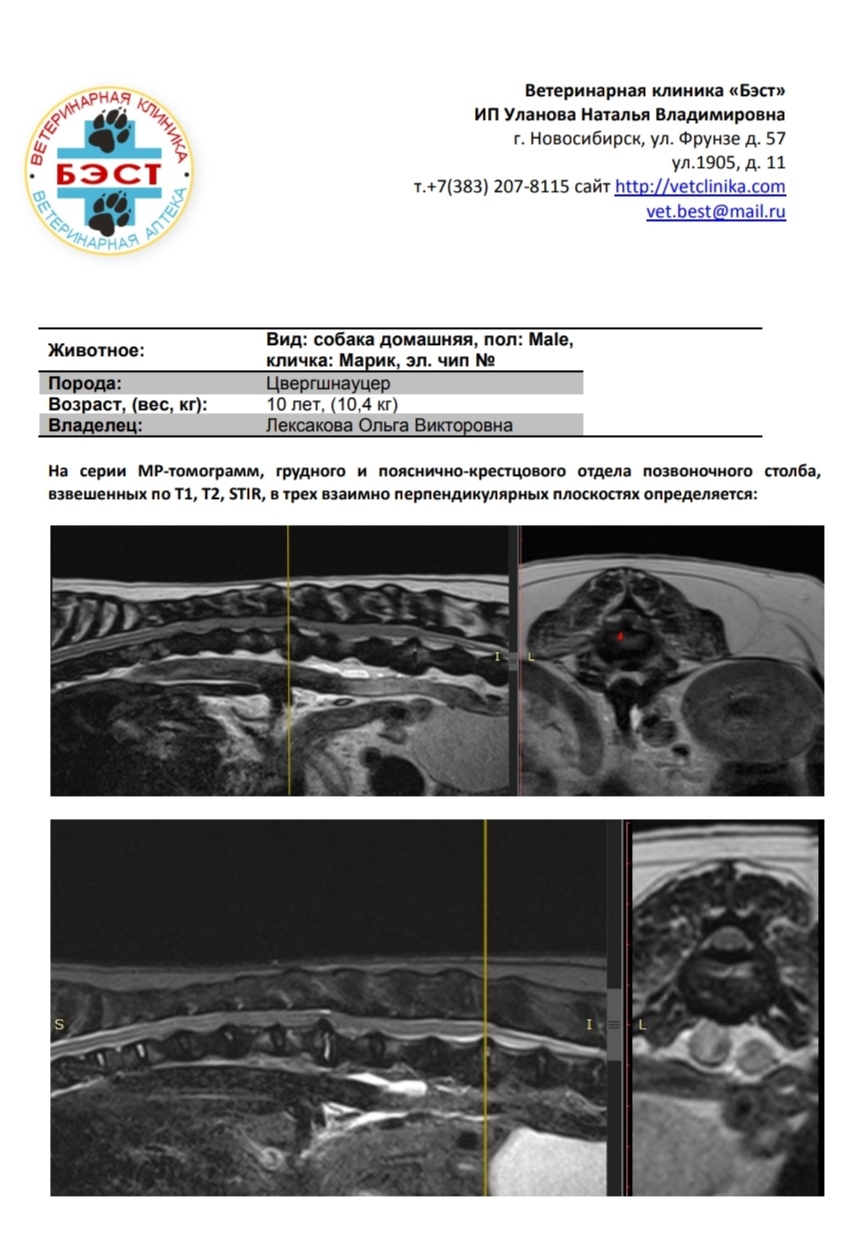

МРТ

Вложения

IMG_20241123_141047.jpg

IMG_20241123_141007.jpg